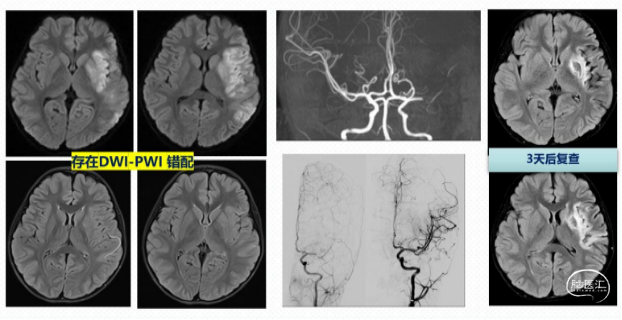

组织窗评估—DWI-PWI 错配

核心梗死区:ADC 值<600 秒/mm2的 DWI 高信号区域。

低灌注区:Tmax>6 秒,或 rMTT 值>145%对侧正常脑组织。

典型病例: 男,61岁,左侧肢体无力3d余,加重伴言语不利10h